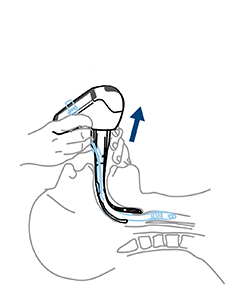

Location of glottic structures

If vocal cords are not seen it is very likely that Airtraq has been inserted TOO DEEP, if so perform the following maneuver:

A gent lift of the Airtraq causes the glottis to open and drops the interarytenoid notch below the middle of the image (optimal position for successful ETT insertion)